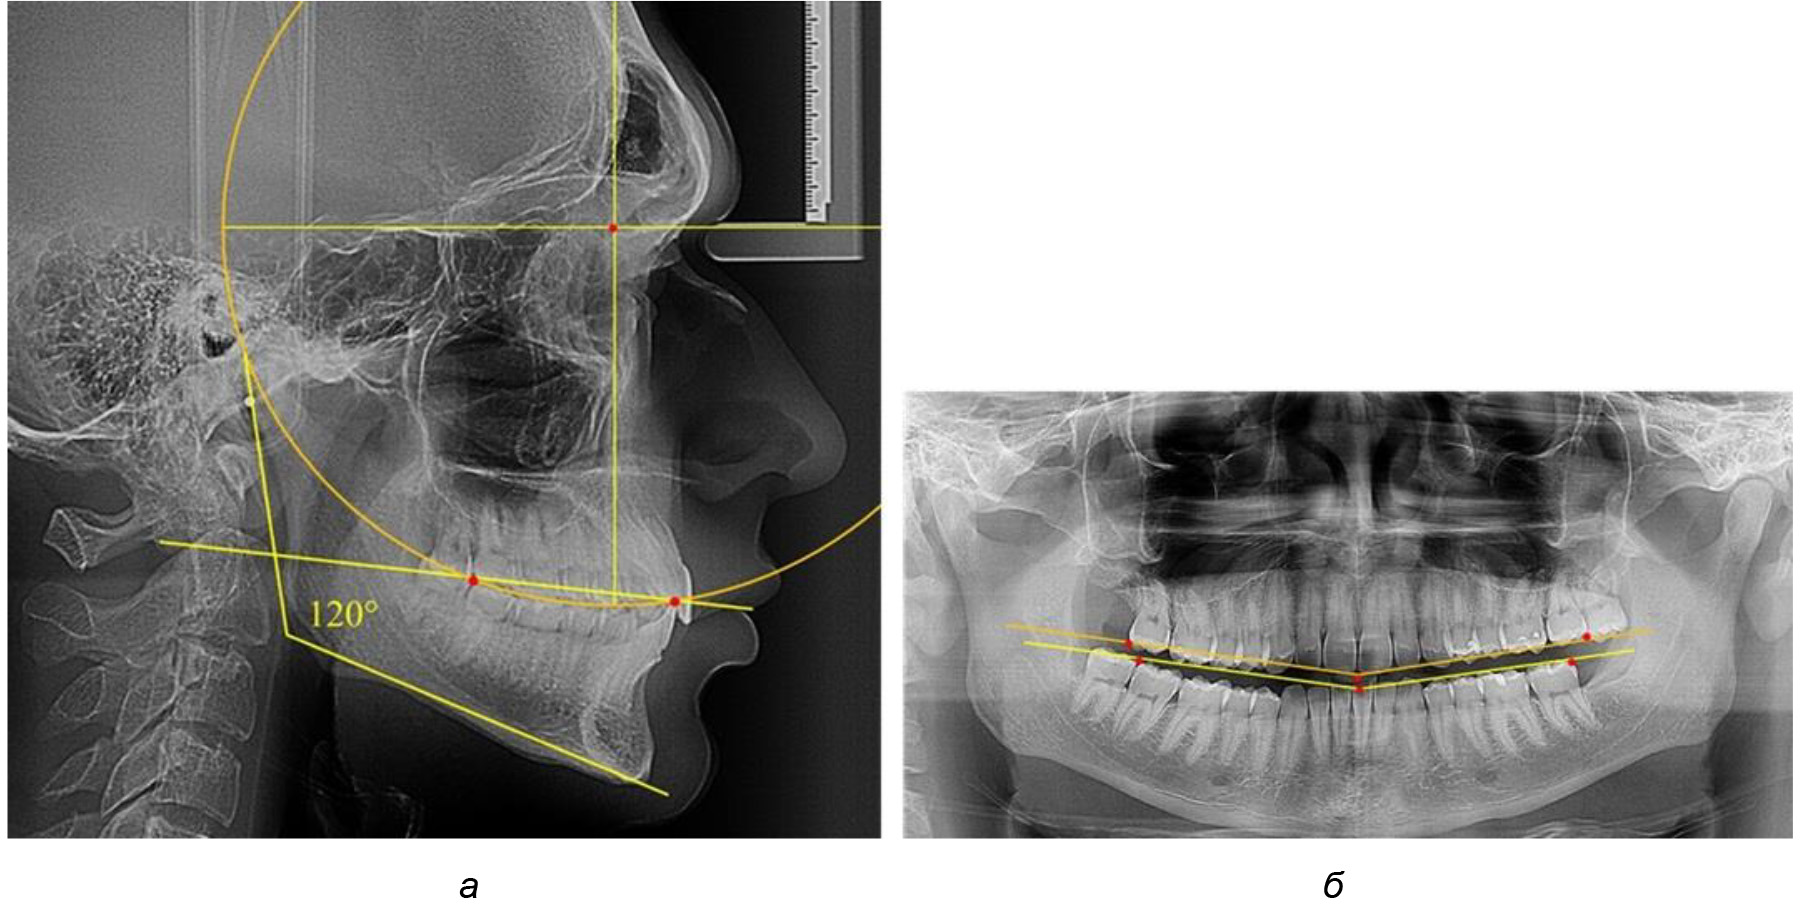

В 3-ю подгруппу вошли ТРГ и ОПТГ 14 человек 1-й группы, что составило (22,58 ± 5,31) % от общего количества людей 1-й группы. Величина угла нижней челюсти в среднем составила (114,85 ± 2,87)° и характеризовала горизонтальный тип нижней челюсти.

Глубина кривой Spee в среднем по 2-й подгруппе составил (2,94 ± 0,47) мм, что было меньше, чем в других подгруппах. Деление величины радиуса круга к длине окклюзионной линии составило 1,616 ± 0,02 (рис. 4).

Рис. 4. Особенности кривой Spee на ТРГ (а) и ОПТГ (б) у людей с горизонтальным типом лица